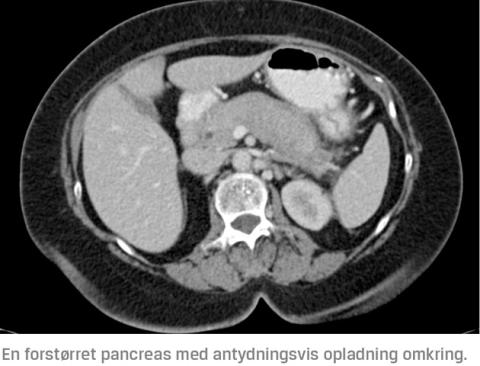

Billeddiagnostik

Det er hyppigst fund ved MR-skanning eller CT, der leder til mistanke om AIP. De to AIP-typer kan ikke adskilles ved skanning. En fokalt eller diffust forstørret pancreas, specielt med en kapsellignende forandring omkring sig, uden dilatation af ductus pancreaticus bør rejse mistanke om AIP [1]. Diffus forstørrelse af hele pankreas findes hos 30-40% af patienterne [4-6, 12], fokal forstørrelse hos 35-75% [4-6, 12], kapsellignende forandring hos 30-48% [4, 12] og forsinket opladning hos ~ 90% [12]. Ovennævnte fund kan gøres ved både MR-skanning og CT, men specielt MR-skanningens T1- og T2-vægtede billeder er vigtige ved diagnostikken af AIP [13]. Forandringer, der er forenelige med AIP, er næsten altid hypointense på T1-vægtede billeder og hyperintense på T2-vægtede billeder.